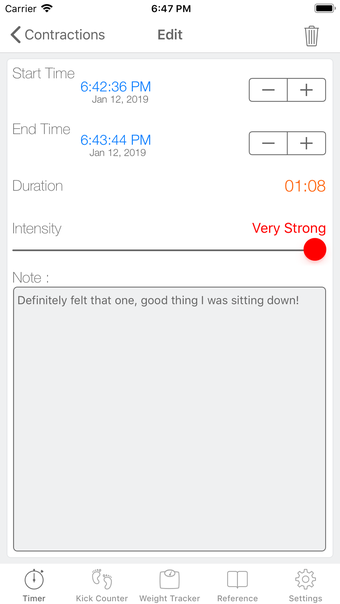

이 어플리케이션은 분만 진행 상황을 명확하게 보여주며, 현재 분만 단계, 이전 및 현재 수축의 시작 및 종료 시간을 보여줍니다. Full Term은 수동으로 각 수축을 시작하고 중지할 필요가 없으며, 어플리케이션을 재시작하더라도 분만 기록을 추적합니다.